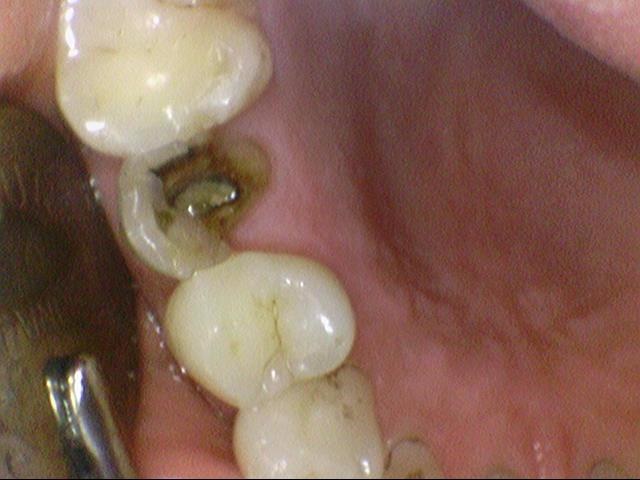

신경치료하고 크라운 안 한 치아->파절

위의 케이스도 비슷합니다.

신경치료를 외국에서 했는데 외국에서는 크라운 비용이 더 비싸다보니 방치해서

크라운으로 치아를 감싸지 못해 치아가 다 부러지고 저렇게 뿌리부분만 남아

크라운조차 할 수 없는 경우가 많습니다.